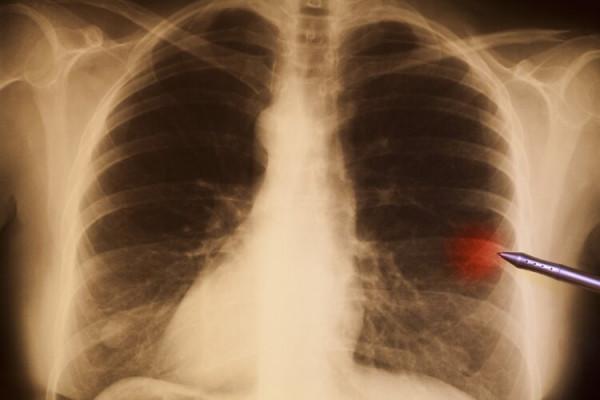

肺結節是指肺部直徑小於3釐米的結節,CT表現為類圓形實性或非實性包塊。

二、如何判斷肺結節是良性還是惡性?

那麼,如何判斷肺結節是良性還是惡性?

很多人會以肺結節的大小為標準,崔飛醫生反駁說:“這是非常片面的。除了大小,還要觀察肺結節的形態和密度,是有實性的成分還是磨玻璃。如果是磨玻璃結節,一般建議在8毫米以上才處理,尤其是純磨玻璃結節,因此需要綜合多個標準去判斷。”